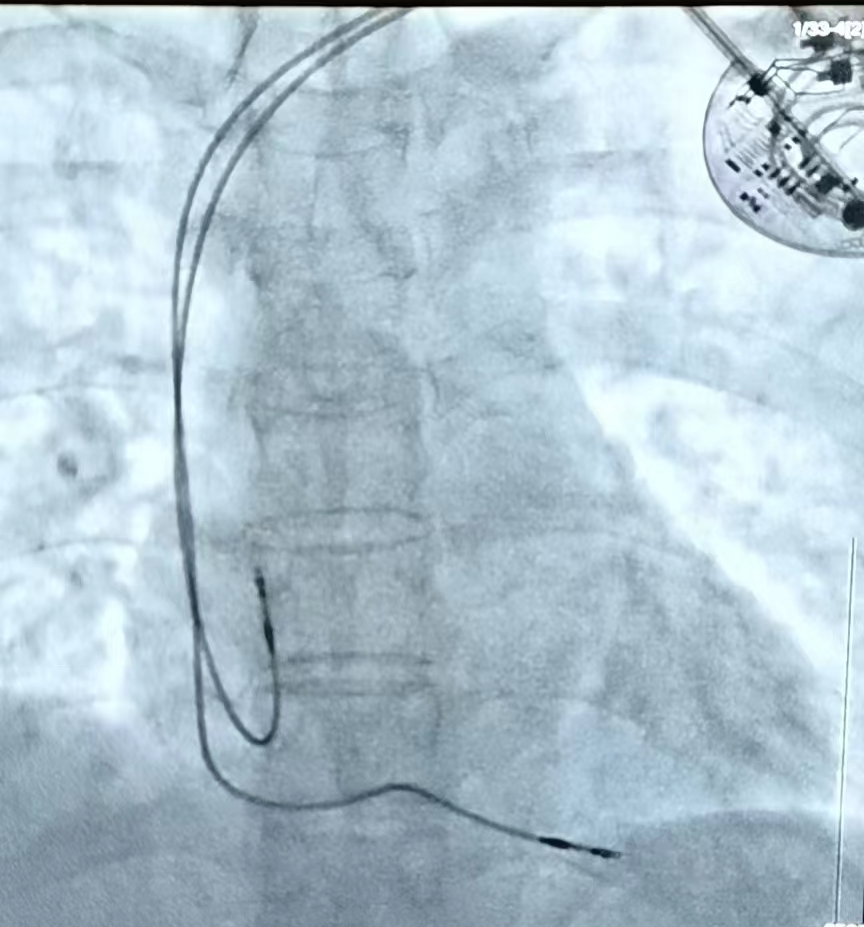

7月12日,石闯教授团队在局麻下,十分顺利地为患者施行了心脏永久双腔起搏器植入术。术后患者心脏恢复正常节律,心率由40次/分升至60次/分,全身血液循环得到改善,患者头晕、乏力等症状明显减轻,无晕厥发作,同时也避免心脏停跳而危及生命的风险。